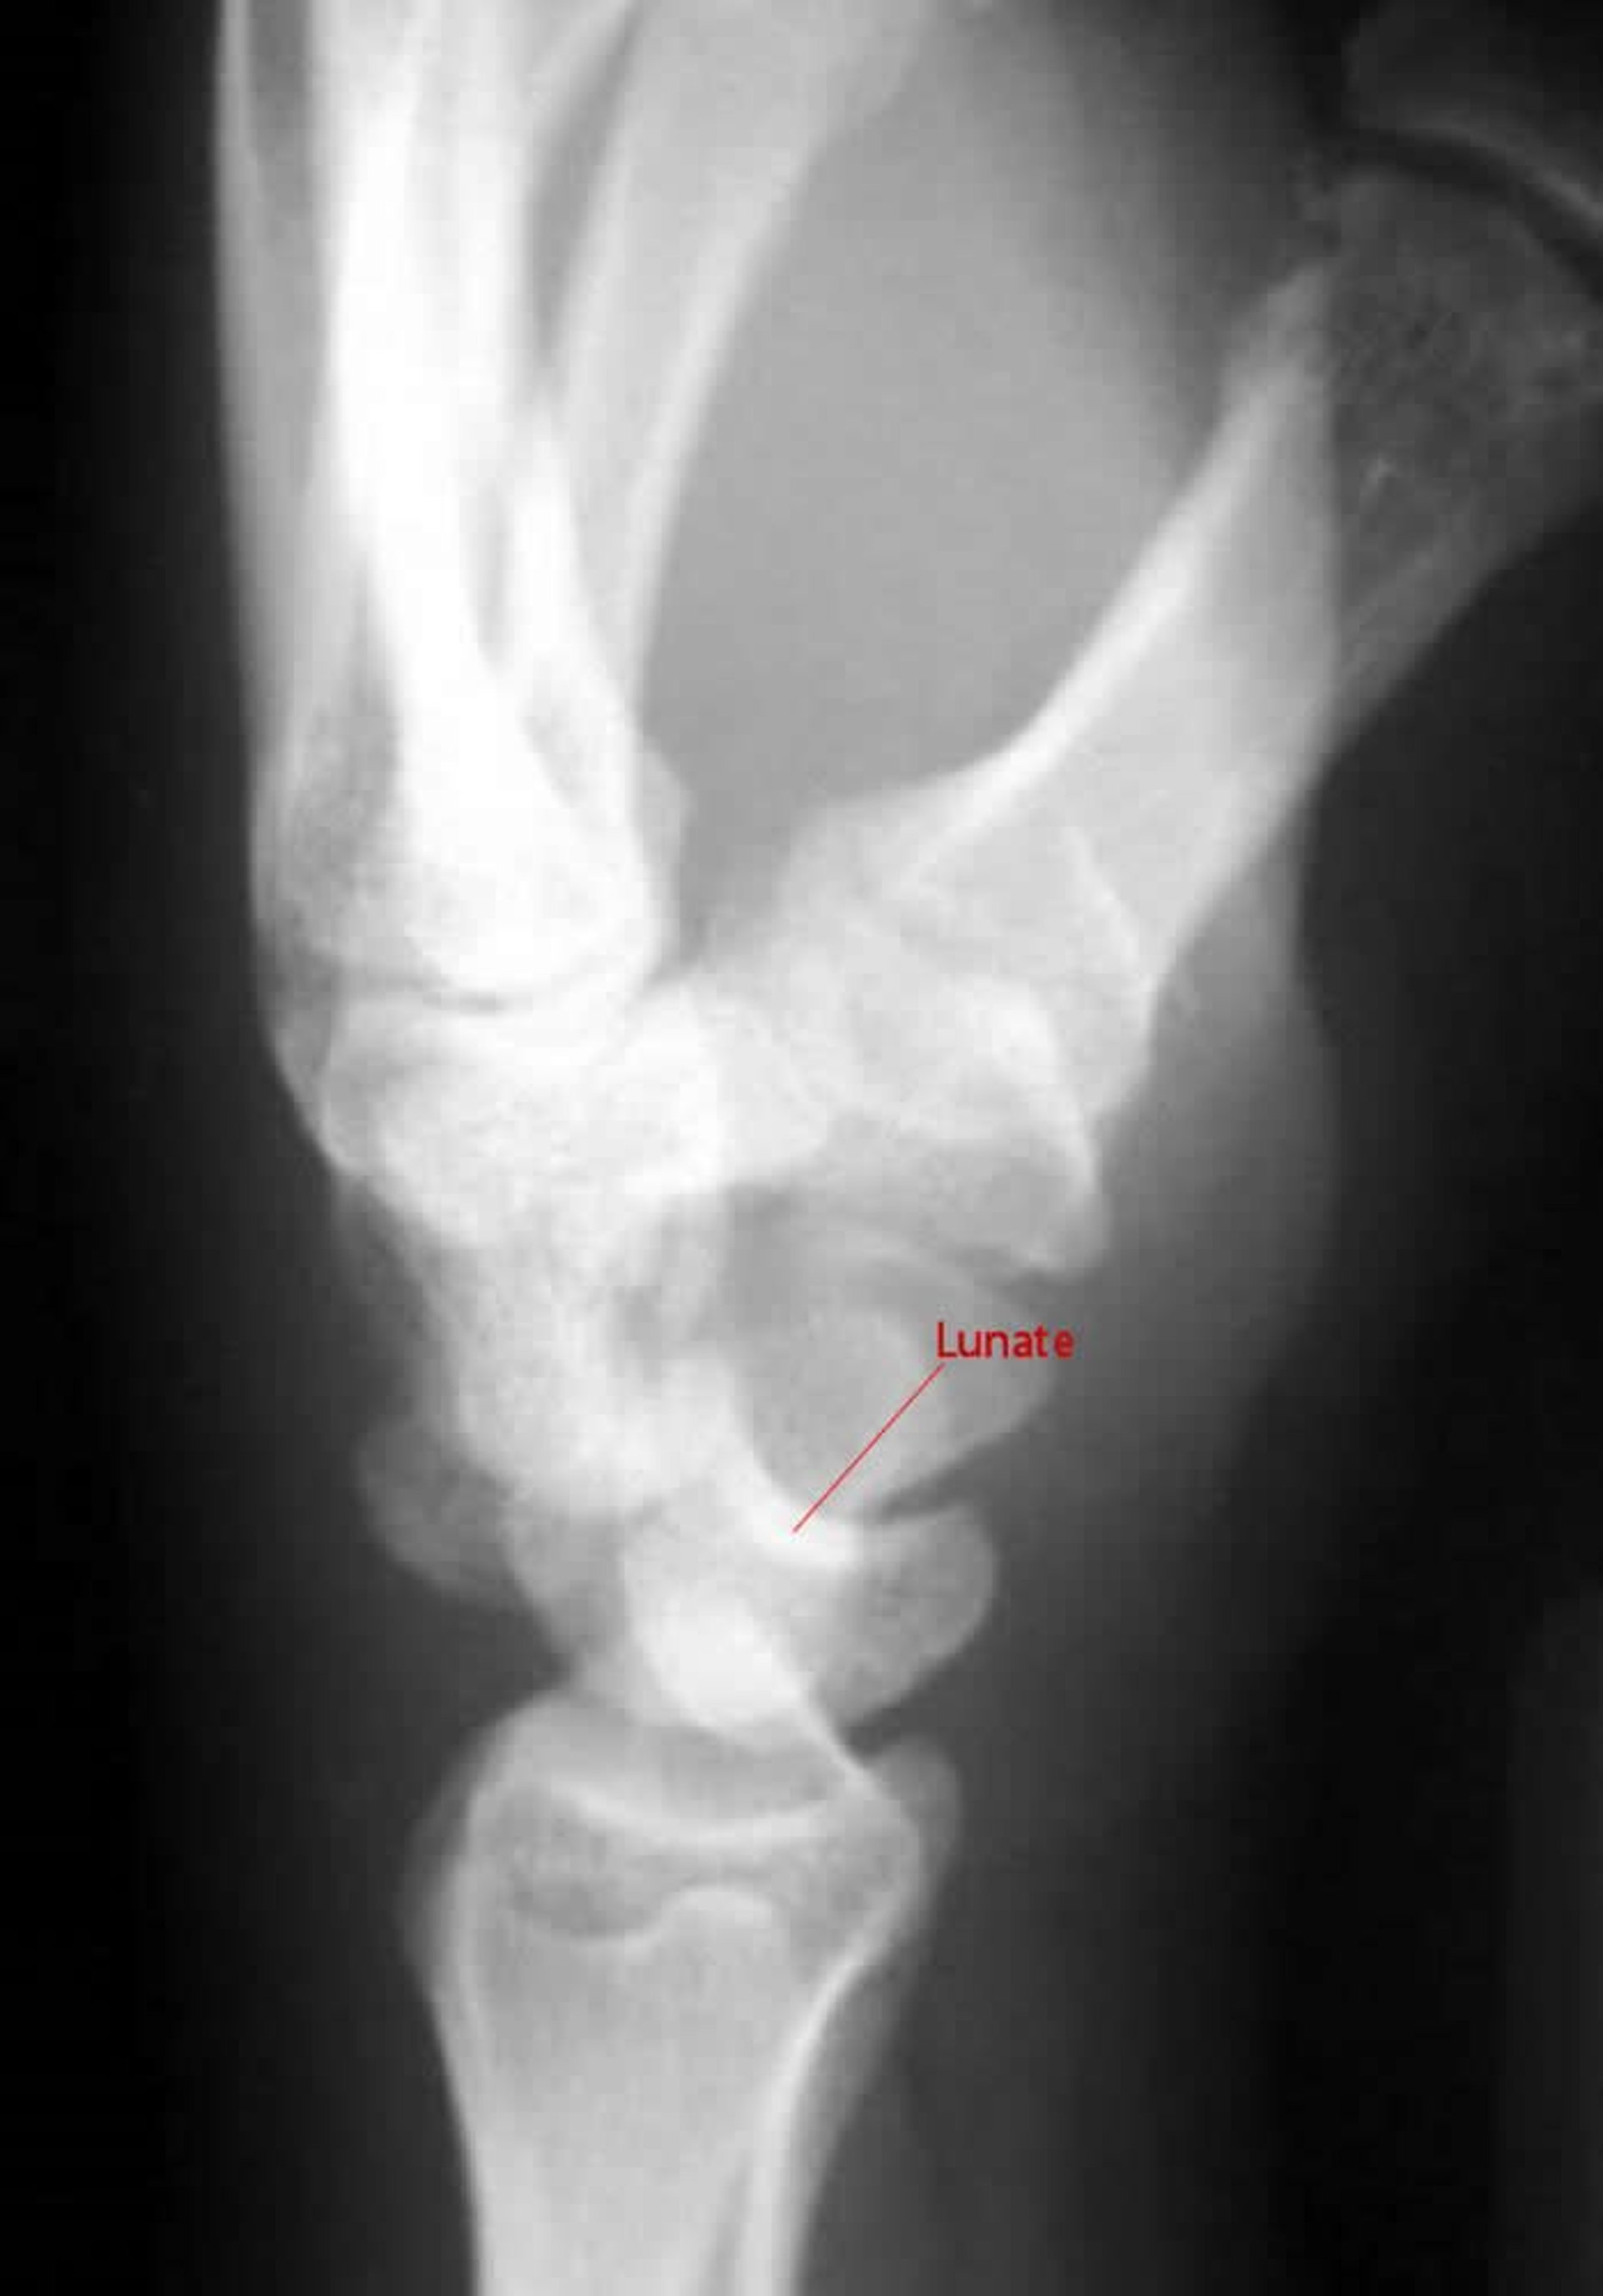

Luxation péri-lunaire

Sur une incidence latérale d'une luxation péri-lunaire, le capité ne s'articule pas avec le semi-lunaire.

Image courtoisie de Danielle Campagne, MD.